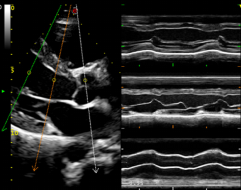

这套超声系统拥有完整的心脏功能检测方案。搭 载更加宽频的相控阵探头,拥有更加完善的小动物心 脏超声解决方案。可以进行心脏解剖 M 型(CMM) , M 型取样线可 360 度任意旋转,并可同时设定 3 条自 由角度取样线。同时显示同一时相 3 条线上组织 M 型 信息,实现在同一个心动周期中,在同一时相对不同 的心肌节段、瓣膜进行对比观察和测量分析。

心脏解剖 M 型(CMM):

M 型取样线可 360 度任意旋转,并可同时设定 3 条自由角度取样线。同时显示 同一时相 3 条线上组织 M 型信息,实现在同一个心动周期中,在同一时相对不同的 心肌节段、瓣膜进行对比观察和测量分析。可应用于心脏和腹部探头(心脏功能评估)。

小鼠左室长轴

小鼠心脏